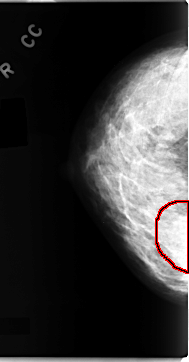

C_0098_1.RIGHT_CC

RIGHT_CC LINES 4704 PIXELS_PER_LINE 2456 BITS_PER_PIXEL 12 RESOLUTION 50 OVERLAY

FILE: C_0098_1.RIGHT_CC.OVERLAY

TOTAL_ABNORMALITIES 1

ABNORMALITY 1

LESION_TYPE MASS SHAPE IRREGULAR MARGINS ILL_DEFINED

ASSESSMENT 4

SUBTLETY 3

PATHOLOGY MALIGNANT

TOTAL_OUTLINES 1

BOUNDARY